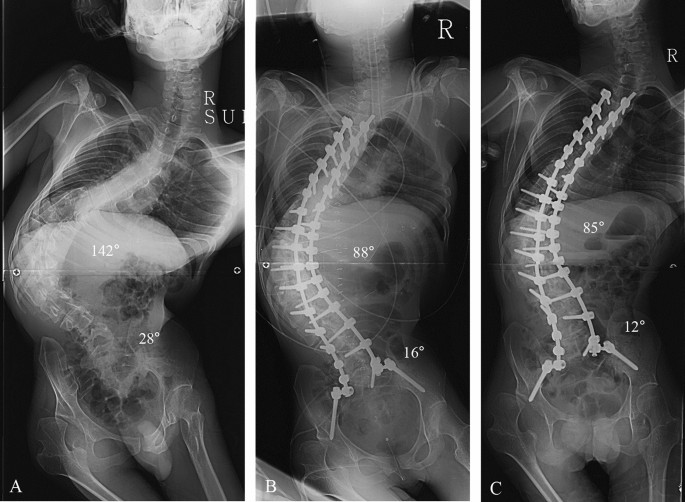

جراحة تثبيت العمود الفقري هي عملية تهدف إلى تقويم الانحناء وتثبيت الفقرات في وضع أكثر استقامة.

- تعديل شكل العمود الفقري

- تثبيت الفقرات باستخدام شرائح ومسامير

- منع زيادة الاعوجاج مع الوقت

الهدف الأساسي ليس فقط تحسين الشكل الخارجي، بل أيضًا تحسين وظائف الجسم اليومية، مثل الجلوس والراحة.

- زيادة سريعة في درجة الاعوجاج